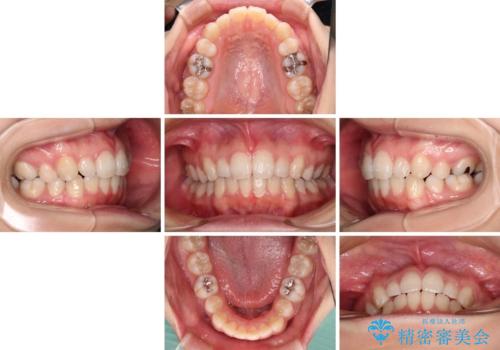

治療途中、妊娠・出産があり、1年近く治療が停滞しましたが、無事に終了することができました。

インビザライン・ライトは提供されるマウスピースの数に制限があり、通常のタイプよりもマウスピース提供期間が短くなっている一方、安価に治療を行うことができるプランです。

治療のゴールも変更できないため、軽微な歯列不正や、後戻り改善などに適しています。